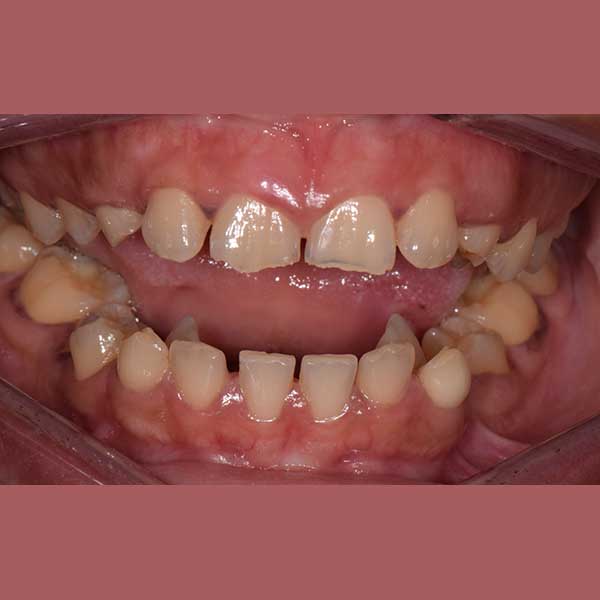

AFTER

By examining the case and taking X-rays, I observed the upper canines in her mouth, and an embedded lower premolar was observed too on the left side, I started the treat the case, but because of the old age of this lady, the upper canines and the left lower premolar did not erupt on their own after we extracted the temporary canines, and she had to pull them out by braces. As for the lower jaw; The canines were pulled back in place and the embedded premolar was orthodontically pulled.

At the end of treatment she asked me to photograph her on her own, because she was happy, and she was able to smile confidently again!